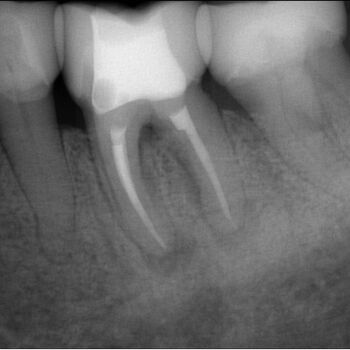

Fall 2: Entfernung eines Instrumentenfragmentes

Röntgenbild: Instrumentenfragment Ausgangssituation

Ausgangssituation